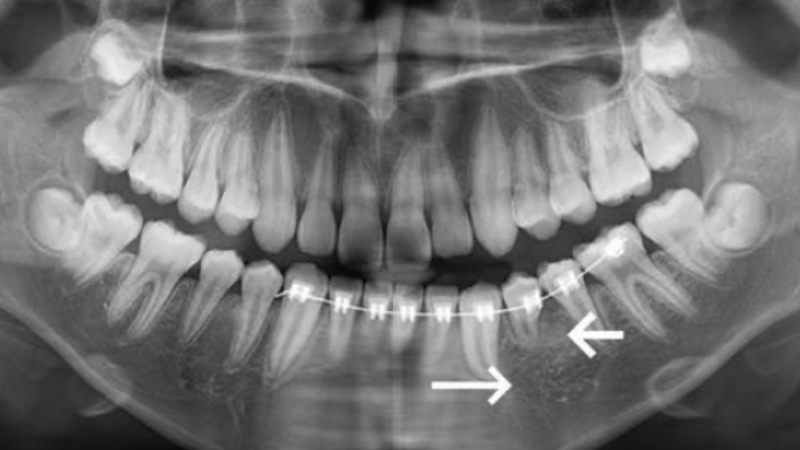

- Przypadek 11-letniego chłopca, u którego zastosowano odbarczenie i drenaż torbieli korzeniowej przy zębie mlecznym.

- Opis sprowadzenia zęba stałego z dilaceracją korzenia do łuku.

Streszczenie: Torbiele korzeniowe są najczęstszymi zapalnymi torbielami zębopochodnymi w jamie ustnej. Torbiele korzeniowe zębów mlecznych mogą prowadzić do dilaceracji korzenia przyszłego zęba stałego, skutkując zatrzymaniem zęba stałego. Przedstawiamy przypadek 11-letniego chłopca, u którego wykonano odbarczenie i drenaż torbieli korzeniowej zęba mlecznego, a następnie dokonano wczesnej ortodontycznej trakcji zęba z dilaceracją korzenia. Torbiel wygoiła się w pełni, a zatrzymany ząb przedtrzonowy został stopniowo wprowadzony do łuku z uzyskaniem korzystnego rozwoju korzenia. Przypadek ten pokazuje, że wykonane na czas odbarczenie torbieli zęba mlecznego może skutecznie ochronić ząb stały. Ponadto w przypadkach, w których doszło już do zatrzymania zęba stałego z [...]